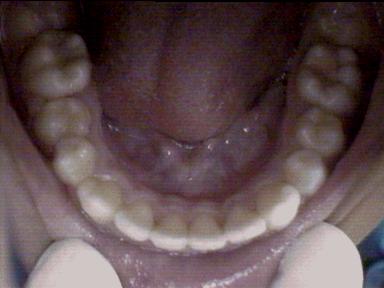

Before Treatment Intra Oral

After Treatment Intra Oral